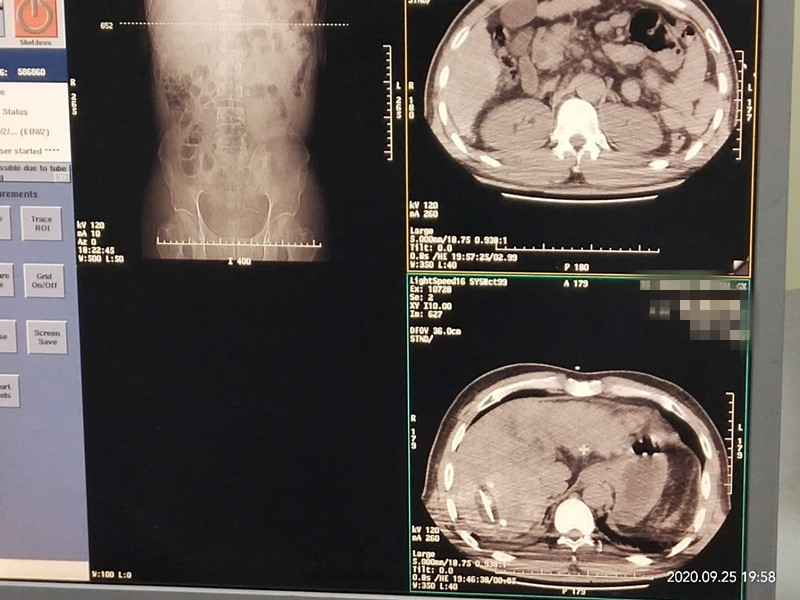

53岁患者肝部氩氦刀冷冻消融

发布人:美国氩氦刀技术官方网站    发布时间:2020/9/29 15:19:10